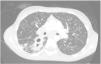

L. was diagnosed with Crohn's disease at the age of 7. She was first treated with oral corticosteroids for 9 months, then azathioprine. Because of persistent symptoms, anti-tumor necrosis factor agents (first infliximab during 3 years, and then adalimumab for 6 months) were added to azathioprine. The child had received BCG vaccination when aged 2 months. The tuberculin skin test was negative, and IGRAs (interferon gamma release assays=QuantiFERON-TB-Gold Cellestis) results were indeterminate before starting anti TNF agents. Abdominal pain, diarrhea, with evening rise fever were persistent despite anti TNF agents. One month after adalimumab was dropped when the child was eleven; ustekinumab treatment was started together with azathioprine, after a collective decision of pediatric and adult gastroenterologists (Fig. 1). No chest X-ray was performed before starting ustekinumab. It was started after 15 days of oral corticosteroids (budesonide 9mg per day). Fifteen days after the first injection of ustekinumab (6mg/kg intravenously), she was referred to our pediatric pulmonology unit for persistent fever, dry cough and weight loss. On clinical examination: oxygen pulse oximetry: 97% (room air); temperature: 39°C; no tachypnea or retraction signs; auscultation showed crackles in the right inferior lobe. Chest X-ray (Fig. 2) showed diffuse alveolo-interstitial opacities, with right parahilar consolidation with central cavitation that is over the helium of 51mm×36mm, and nodules with diffuse distribution of 2–4mm. Blood test showed moderate inflammation (C-reactive protein 80mg/l). Viral and bacterial nasopharyngeal aspirates were negative (Mycoplasma and Chlamydia pneumoniae, multiplex viral PCR). Fiberoptic bronchoscopy showed obstruction of the apical bronchi of the right inferior lobe by endobronchial granuloma. Broncho alveolar lavage showed normal cellularity, with lymphocytosis (=135cells/mm3, with 33% macrophages, 51% lymphocytes, 16% neutrophils). Bacterial culture was negative, as well as respiratory viruses and mycology culture (Pneumocystis jirovecii) on BAL. Acid fast bacilli (AFB) was detected by microscopy using Ziehl Neelsen stain on BAL, sputum smear and post bronchoscopy gastric aspirate. Culture grew for multisensible Mycobacterium tuberculosis. At that time, tuberculin skin test was negative, and IGRA (QuantiFERON-TB-Gold Cellestis) was indeterminate. There were no close contacts with tuberculosis. Thoracic computed tomodensitometry (Fig. 3) was consistent with disseminated tuberculosis. In both lungs there are multiple nodules being the largest in the superior segment of the right lobe where there are bigger than those located in other lobes; multiple adenopathy in the right hilar and interlobar regions; and condensation of 35mm×26mm of the apical segment of the right inferior lobe, with two central excavation of 12mm×5mm and 10mm×7mm.

This is the first case described of disseminated TB in a child under ustekinumab for Chron's disease. Disseminated TB in this child was suspected on chest X-ray (and CT scan) and confirmed by the presence of Mycobacterium tuberculosis on sputum smear, BAL, and post FB gastric aspirate.